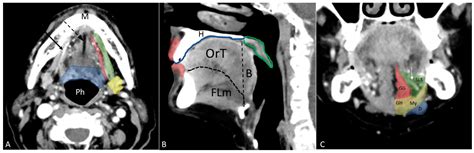

• Physical Examination: A thorough examination of the mouth, including the floor of the mouth, tongue, and throat.

• Imaging Tests: X-rays, CT scans, MRI, or PET scans may be used to determine the extent of the cancer and whether it has spread.